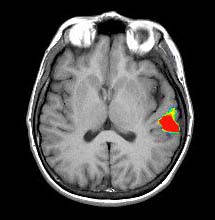

Studies in Late Bilinguals

Right handed 34 year-old-woman. Native language: Spanish

| Paradigm |

Type: Verbal fluency task

ON: Retrieve verbs related to presented nouns

OFF Spell given words |

| Statistics |

| Statistical method |

P Value |

Z score |

| T-Test |

0.0001 |

3.8 |

| Images |

Spanish

English

| Activation |

There is activation of Broca's area in both languages. The right thalamic activation is noted only in the second language. There is also greater activation of the right inferior frontal gyrus in the second language than in the mother language. SMA is more pronounced on the right in both languages. |